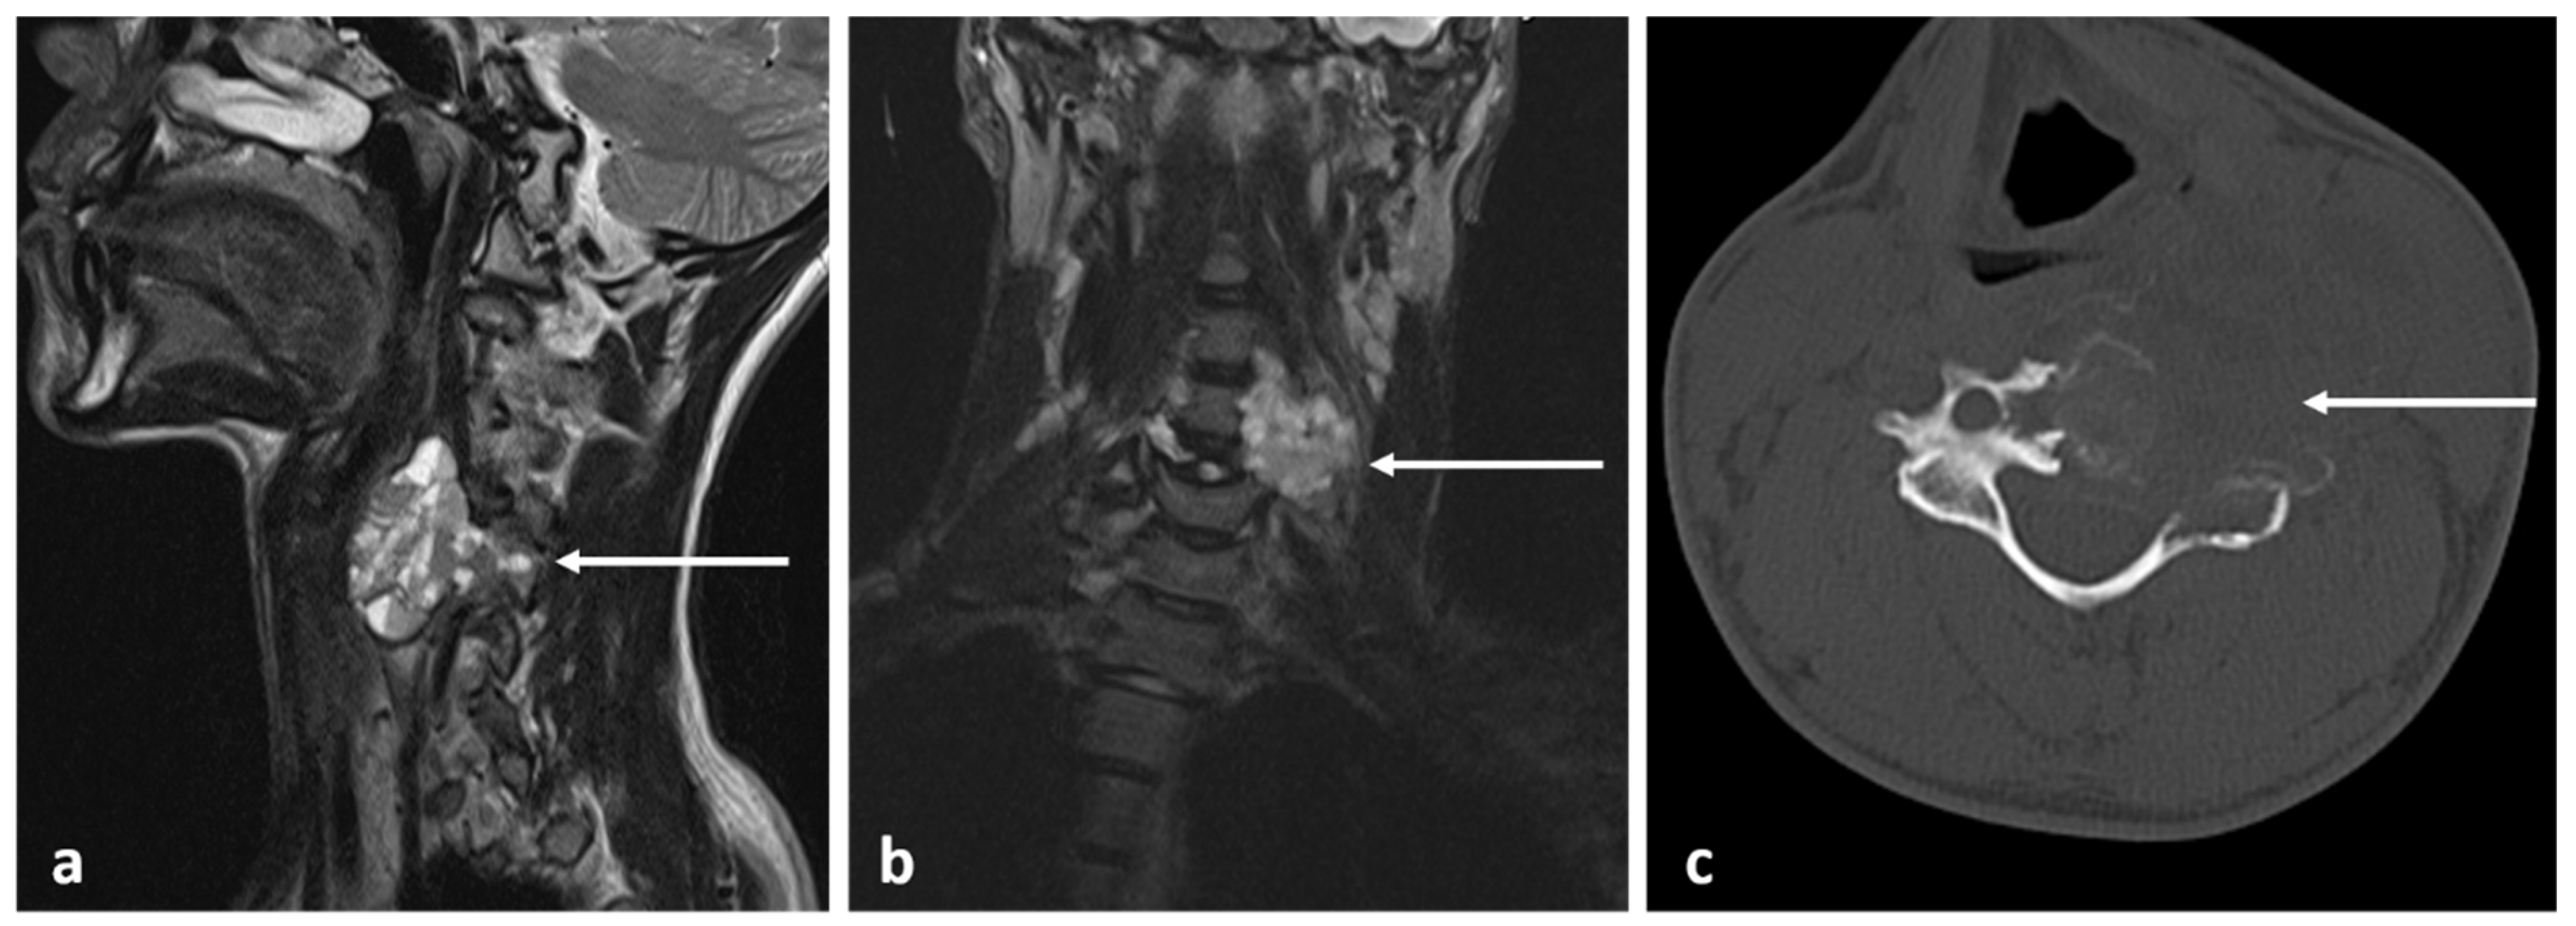

3.3. Osteoblastoma

| Osteoblastoma | Expansile lucent lesion. Sclerotic rim. Bone destruction. Variable intralesional ossification. | Low to intermediate T1 signal and intermediate to high T2 signal. Surrounding soft tissue oedema, extra osseous soft tissue component. |